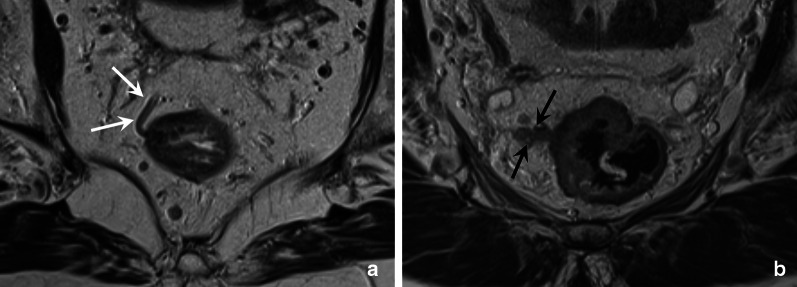

Small mesorectal vasculature and extramural vascular invasion (EMVI)

In addition to the larger arteries and veins described in the previous section, there are also numerous unnamed smaller vessels that radiate outwards from the edge of the muscularis propria into the perirectal fat. These smaller vessels can be visualised as small serpiginous branches, as illustrated in Fig. 11A. Extramural vascular invasion (EMVI) can occur in tumours that grow beyond the muscularis propria (≥ T3) and is defined as the extension of tumour within these small perirectal blood vessels [32]. It is a known adverse prognostic risk factor associated with recurrent disease, metastases and impaired overall survival [33]. On MRI, EMVI can be visualised as direct tumour signal extending into a blood vessel, with or without expansion of the vessel or infiltration of the vessels borders (Fig. 11B).

Fig. 11.

Axial T2-weighted images of two rectal cancer patients; a 63-year-old male patient with a cT1-2 rectal tumour (a; tumour not shown) an another 83-year-old female patient with a cT3cd tumour (b). The image in A is a cross section just above the level of the tumour in the rectal wall and shows a small vessel radiating outwards from the muscularis propria into the perirectal fat (white arrows). The vessel has a normal contour and low T2 signal; there are no signs of EMVI. The image in b shows a semicircular tumour that involves the rectal wall from 7 till 1 o’clock. The intermediate signal of the tumour extends into the adjacent vessels. The vessels is expanded, and the vessel contour is disrupted. These are all signs indicative of EMVI